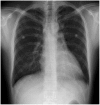

Pneumopericardium is a rare complication of pericardiocentesis, occurring either as a result of direct pleuro-pericardial communication or a leaky drainage system. Air-fluid level surrounding the heart shadow within the pericardium on a chest X-ray is an early observation at diagnosis. This clinical measurement and process is variable, depending on the hemodynamic status of the patient. The development of a cardiac tamponade is a serious complication, necessitating prompt recognition and treatment. We recently observed a case of pneumopericardium after a therapeutic pericardiocentesis in a 20-year-old man with tuberculous pericardial effusion.